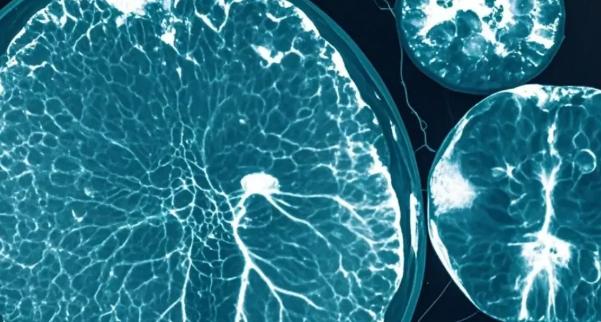

红外滤光片的核心原理是光谱选择性透过,它只允许特定波长的红外光通过,屏蔽干扰光。近红外光谱成像(NIRS),广泛应用于血管成像、肿瘤定位等领域。例如,在乳腺癌筛查中,红外滤光片结合近红外光成像技术,可以无创检测肿瘤的血氧供应情况,帮助医生早期发现病变。